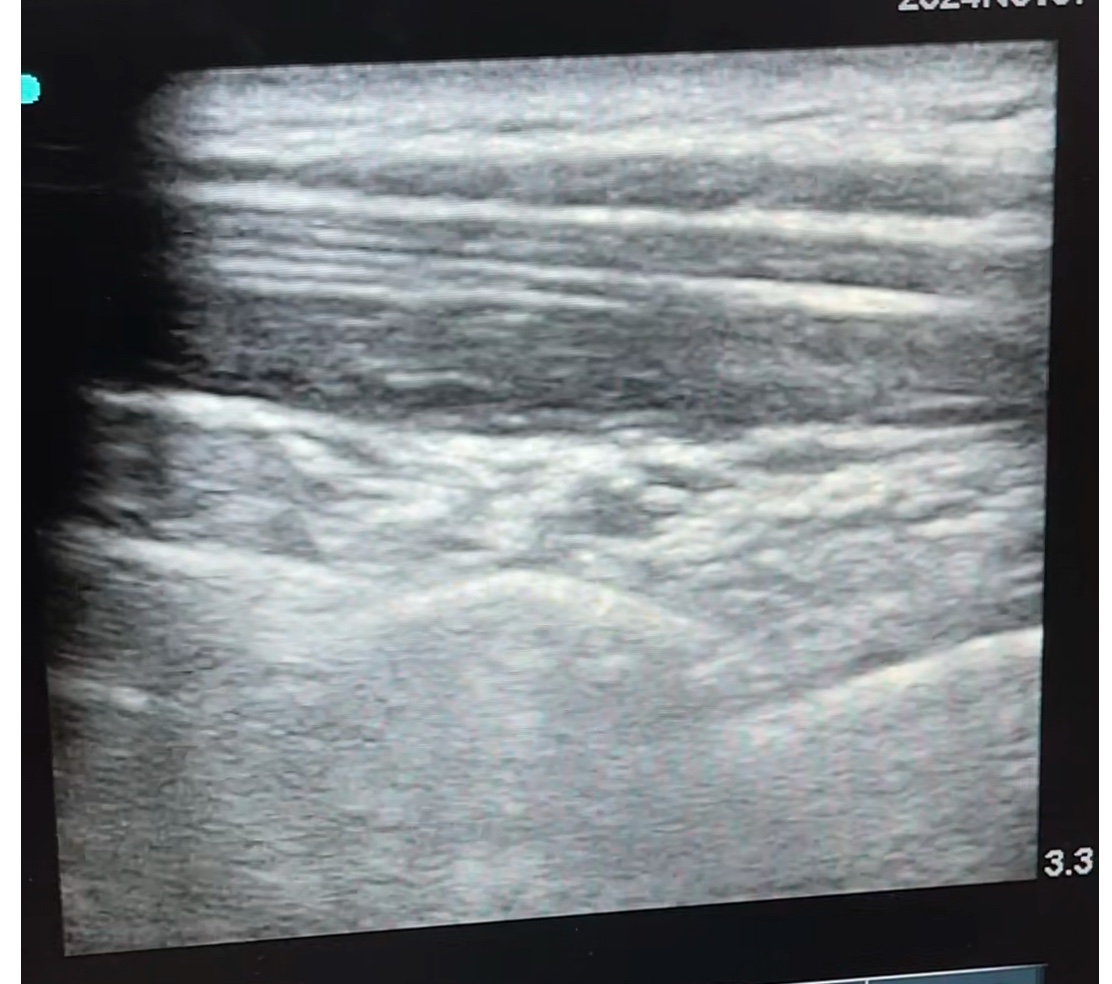

เทคโนโลยี Ultrasound เป็นเครื่องมือที่ช่วยให้แพทย์สามารถเห็นภาพของเนื้อเยื่อและเส้นประสาทในบริเวณที่ต้องการฉีดยาได้อย่างชัดเจน ซึ่งทำให้การฉีดยาลดการอักเสบมีความแม่นยำสูง แพทย์สามารถระบุตำแหน่งที่ต้องการฉีดยาได้ตรงจุดที่มีปัญหามากที่สุด ส่งผลให้การรักษามีประสิทธิภาพและลดความเสี่ยงของการบาดเจ็บต่อเนื้อเยื่อรอบข้าง

การฉีดยาลดการอักเสบด้วย Ultrasound ทำให้ผู้ป่วยไม่ต้องกังวลเรื่องการฉีดยาในตำแหน่งที่ผิดพลาด หรือการบาดเจ็บต่อเส้นประสาทอื่น ๆ และยังช่วยเพิ่มความมั่นใจให้ผู้ป่วยว่าการรักษานั้นเป็นไปอย่างปลอดภัย

2. เตรียมอุปกรณ์และตำแหน่งฉีดยา: แพทย์จะใช้เครื่อง Ultrasound เพื่อระบุตำแหน่งเส้นประสาทและบริเวณที่ต้องฉีดยาอย่างแม่นยำ พร้อมทั้งใช้ยาชาเฉพาะที่เพื่อลดความรู้สึกไม่สบายขณะฉีดยา

3. การฉีดยาลดการอักเสบ: แพทย์จะฉีดยาลดการอักเสบ เช่น สเตียรอยด์หรือยาชาเฉพาะที่ เข้าไปยังบริเวณที่มีการอักเสบโดยตรง ด้วยความแม่นยำสูงจากการใช้ Ultrasound